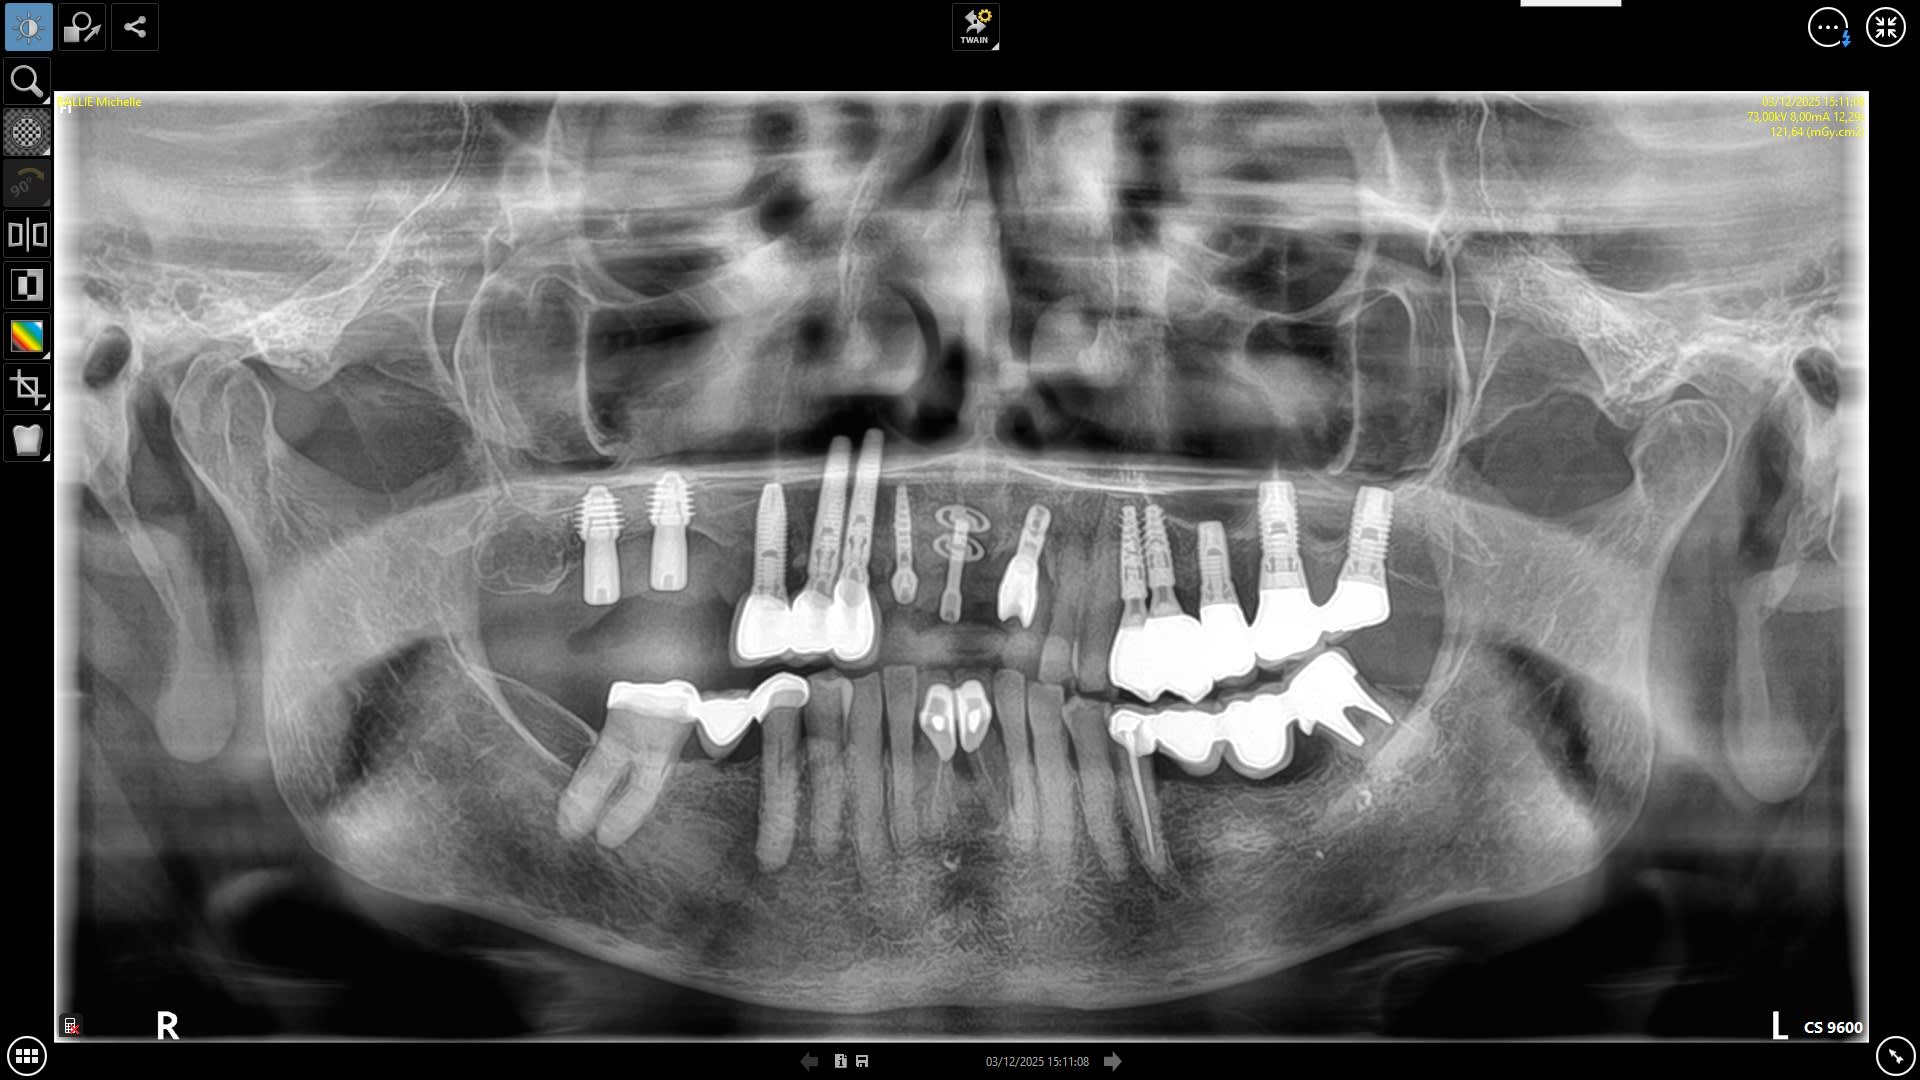

voici un implant en 21 posé il y a 25 ans par le dr Donsimoni à la clinique de l'Europe à Paris (il est agé maintenant de 80 ans ancien expert et retraité, il serait parti avec ses dossiers patients d'après la clinique)

il a posé cet implant en même temps que le diskimplant Victory en 11. je cherche un compatible pour refaire la prothèse. La connexion est un hexagone externe compatible biomet3i, mais pas la vis de pilier dont les spires sont nettement plus serrées.